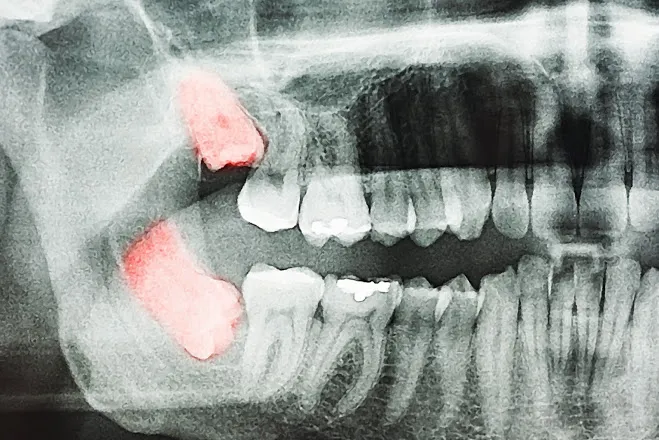

3. Há Inigualáveis "Sisos Muito Mais Complicados"

Toda anatomia esquelética difere! Nunca encare extrações alinhadas as promessas curtas do vizinho como modelo real:

- Os Sisos Simples Padrões: Erguem-se verticais iguais a dentes normais já furando sua gengiva para fora com fácil extração simples de tenaz em dois rápidos minutos inteiros.

- Os Sisos Horizontais Ocultos (Impactados Terceiro Molar): Totalmente "deitados" trancafiados pela espessa cortical óssea, repousando por baixo empurrando raízes mortais dos molares do meio. Nossos cortes demandam longos minutos de blocos secionados, separando delicada raiz por raiz por conta de cruzarem veias maxilares mandibulares nevrálgicas de dor (Eles criam um resguardo forte roxo com restrições difíceis de abrir a fala nos dias de trás).

- Se a imagem da Tomografia revela raízes do terceiro dente completamente alinhadas sem tranco para fora empurrar;